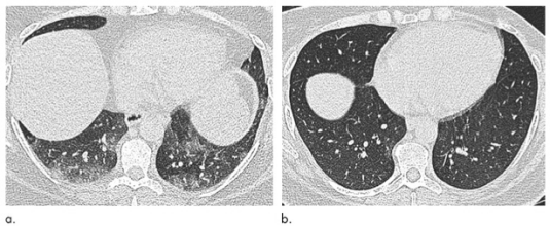

图2 与图1相同的51岁女性肺部轴位呼气末期CT图像,(a)减肥手术前和(b)体重减轻31 kg(体重指数降低31.6%)后6个月,术前患者出现了空气储留,但在手术后消失。请注意,由于膈肌偏移的差异以及由于肥胖引起的肺外限制增加对肺实质的影响,因此手术前后各部分的解剖位置会有所不同。